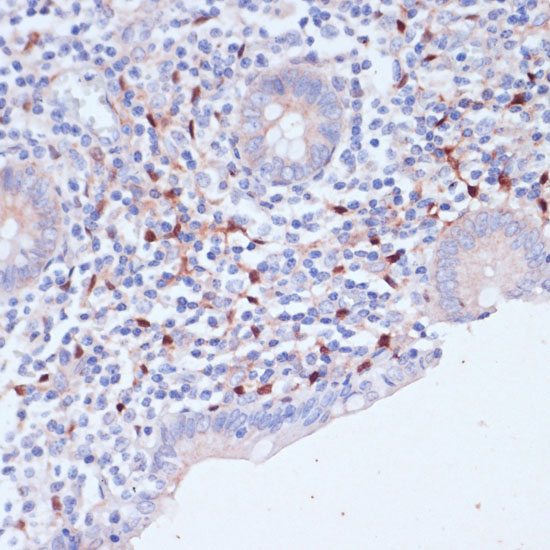

Immunohistochemistry of paraffin-embedded human appendix using WIPF1 antibody.

Immunohistochemistry of paraffin-embedded mouse spleen using WIPF1 antibody.